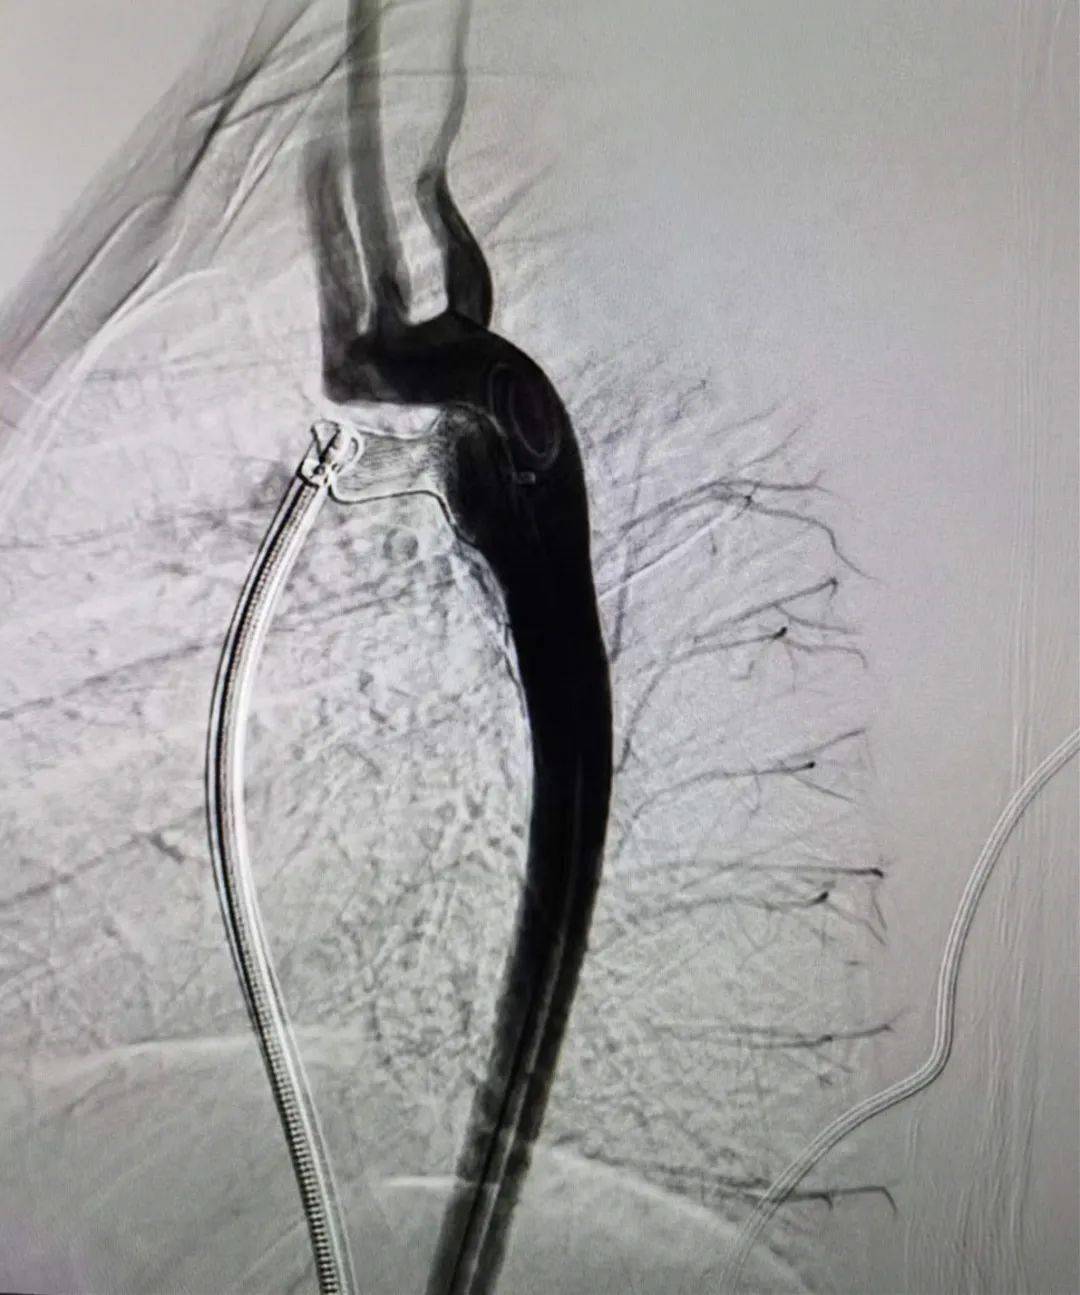

动脉导管未闭装置闭合

为了一个10公斤,1岁的信宜女婴,12mm的巨大动脉导管,肺水肿

济南三院成功开展首例动脉导管未闭封堵术,为患者带来"心"希望!